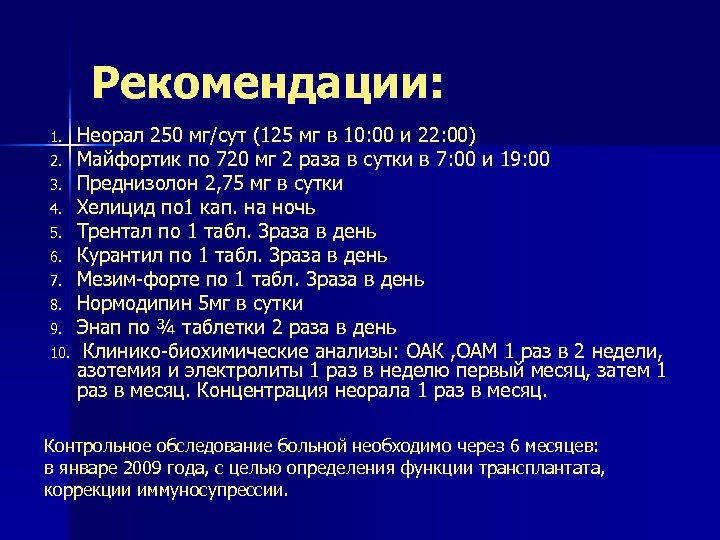

Рекомендации: 1. 2. 3. 4. 5. 6. 7. 8. 9. 10. Неорал 250 мг/сут (125 мг в 10: 00 и 22: 00) Майфортик по 720 мг 2 раза в сутки в 7: 00 и 19: 00 Преднизолон 2, 75 мг в сутки Хелицид по 1 кап. на ночь Трентал по 1 табл. 3 раза в день Курантил по 1 табл. 3 раза в день Мезим-форте по 1 табл. 3 раза в день Нормодипин 5 мг в сутки Энап по ¾ таблетки 2 раза в день Клинико-биохимические анализы: ОАК , ОАМ 1 раз в 2 недели, азотемия и электролиты 1 раз в неделю первый месяц, затем 1 раз в месяц. Концентрация неорала 1 раз в месяц. Контрольное обследование больной необходимо через 6 месяцев: в январе 2009 года, с целью определения функции трансплантата, коррекции иммуносупрессии.

Рекомендации: 1. 2. 3. 4. 5. 6. 7. 8. 9. 10. Неорал 250 мг/сут (125 мг в 10: 00 и 22: 00) Майфортик по 720 мг 2 раза в сутки в 7: 00 и 19: 00 Преднизолон 2, 75 мг в сутки Хелицид по 1 кап. на ночь Трентал по 1 табл. 3 раза в день Курантил по 1 табл. 3 раза в день Мезим-форте по 1 табл. 3 раза в день Нормодипин 5 мг в сутки Энап по ¾ таблетки 2 раза в день Клинико-биохимические анализы: ОАК , ОАМ 1 раз в 2 недели, азотемия и электролиты 1 раз в неделю первый месяц, затем 1 раз в месяц. Концентрация неорала 1 раз в месяц. Контрольное обследование больной необходимо через 6 месяцев: в январе 2009 года, с целью определения функции трансплантата, коррекции иммуносупрессии.